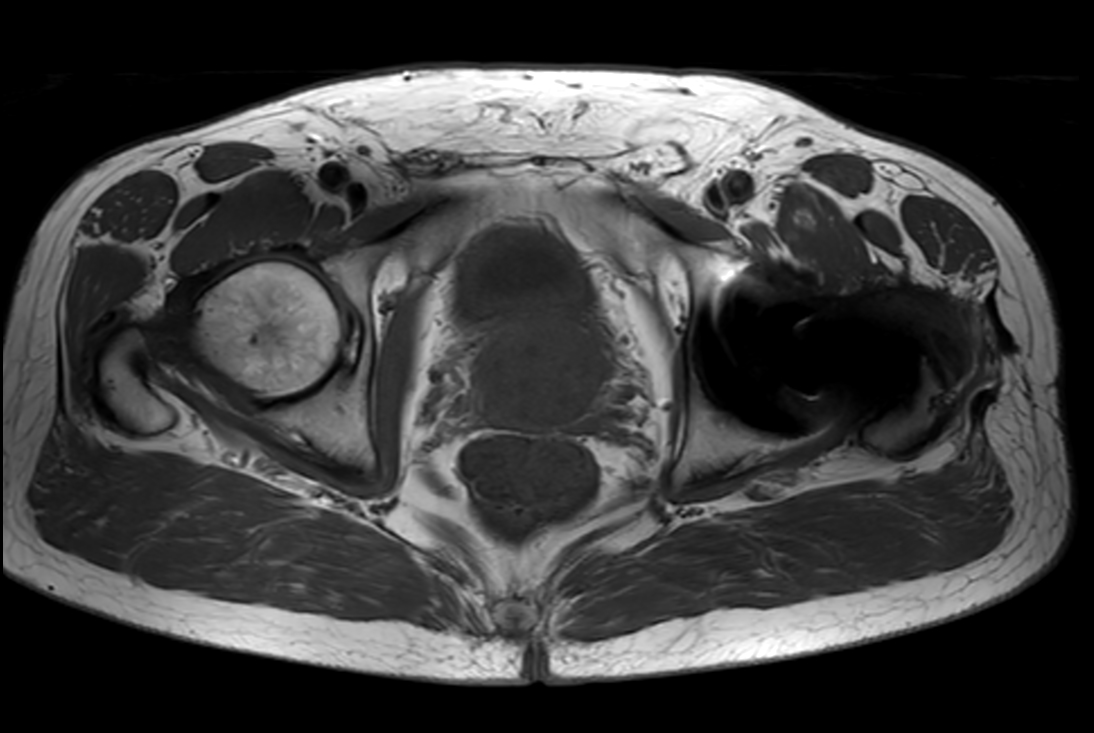

Axial T2w TSE